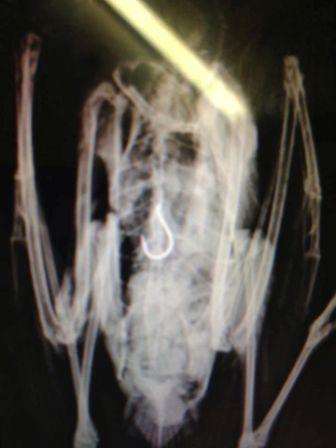

Eating, drinking, picnicking - we all love to do it! Especially in beautiful areas such as the park, the beach and the lake-side. But those areas won't stay beautiful for long if we just toss our garbage on the ground or into the water. This confronting image should be enough to make us all want to clean up our act:

Swamp hen wearing litter... Photo by Andrea Louisa Glazier.

If you're fishing, make sure you take all your fishing hooks and line with you. Many of our sea-birds get horribly entangled in fishing line or swallow fish-hooks that have not been properly discarded.

Radiography of a sea-gull that has ingested a discarded fish-hook.